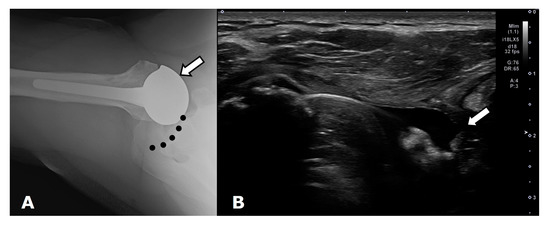

4.2.4. Rotator Cuff Tendon Tears

4.2. General Complications